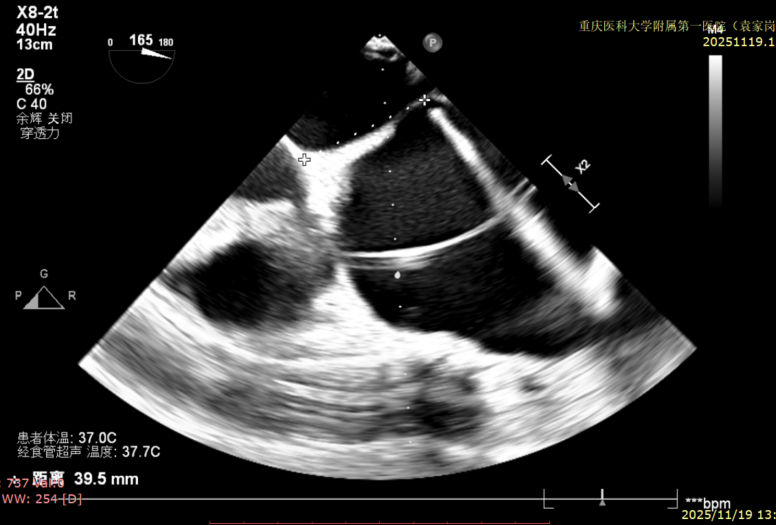

图3:房间隔可用高度>4cm

患者全麻下行TEER手术。向睿副主任团队穿刺患者右侧股静脉,在X线及食道超声指导下完成房间隔穿刺(视频4)成功获得3.95cm穿刺高度(图4)。再将加硬导丝送至左上肺静脉,20F股静脉扩张鞘充分扩张股静脉穿刺部位,沿加硬导丝将可操纵导引导管(SGC)送入左房。延SGC送入XTR夹子完成骑跨,使用M旋钮使夹子指向二尖瓣(图5)(视频5)。调整Mitraclip输送系统顺利到达二尖瓣目标位置,TEE指导下左房内完成弹道测试和Orientation调整(视频6)。缓慢将XTR夹子送入左室,并三维再次确认夹子轴向和反流位置,缓慢上提夹子使夹臂成功捕获瓣叶(视频7),Gripper Down夹持前后瓣叶并缓慢关闭夹臂(视频9),夹持后反流降至微量(视频10),二尖瓣平均跨瓣压差2mmHg(图6)。评估后将夹子释放。释放后反流微量夹子稳定。术后复查超声证实夹合组织充分,显示微量残余分流。术后二尖瓣平均跨瓣压差2mmHg,肺静脉多普勒波形恢复正常。手术时间持续约1.5小时。

图4:穿刺高度3.95cm